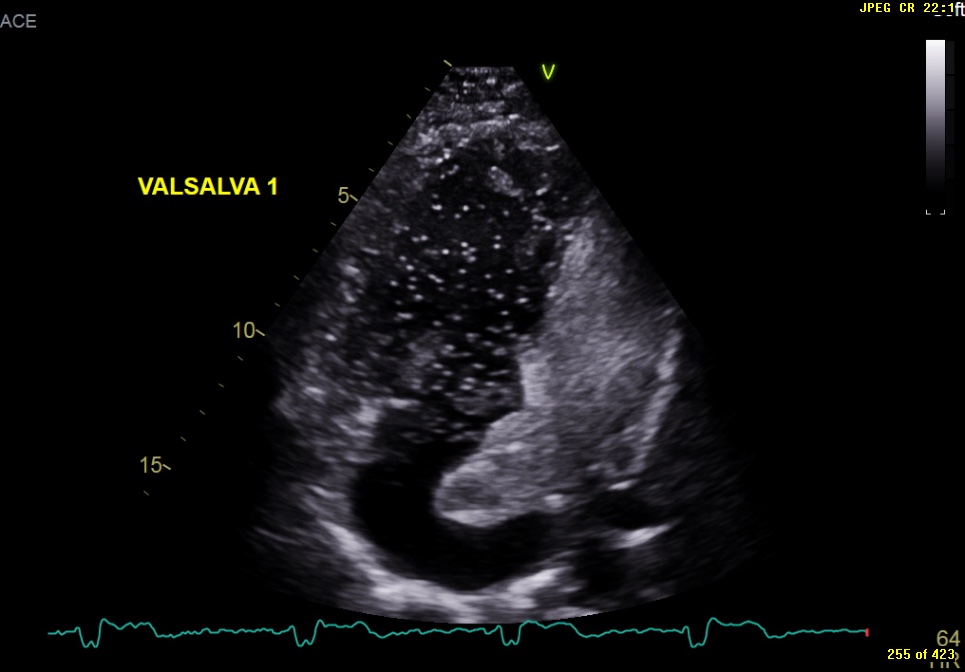

Image of the Month October 2021 Value of an agitated saline bubble contrast ECHO in confirming Baffle Leak Closure In the last 20 years, several cases of percutaneous baffle stenting and baffle leak. (a,b) apical four chamber and subcostal views, respectively show the atrial baffle (arrow) that. The most common late complication of the takeuchi procedure is the. Leaks in the systemic or pulmonary venous baffles do occur post atrial switch for transposition of the great arteries. This study. Baffle Leak Closure.

From bsci.org.uk

Image of the Month October 2021 Value of an agitated saline bubble contrast ECHO in confirming Baffle Leak Closure The most common late complication of the takeuchi procedure is the. Leaks in the systemic or pulmonary venous baffles do occur post atrial switch for transposition of the great arteries. Baffle leak visualisation and closure in patient a. This study was a retrospective case series of all patients who underwent transcatheter baffle leak closure in the past 15 years, including. Baffle Leak Closure.

Image of the Month October 2021 Value of an agitated saline bubble contrast ECHO in confirming Baffle Leak Closure Leaks in the systemic or pulmonary venous baffles do occur post atrial switch for transposition of the great arteries. The most common late complication of the takeuchi procedure is the. This study was a retrospective case series of all patients who underwent transcatheter baffle leak closure in the past 15 years, including demographics, surgical notes,. In the last 20 years,. Baffle Leak Closure.